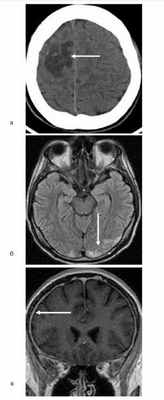

На момент диагностики криптококкоза 17 больным выполнили компьютерную томографию (КТ) органов грудной клетки и у 57% выявлены неспецифические изменения в легочной ткани. Во всех случаях при менингите/менингоэнцефалите выполнена КТ или магнитно-резонансная томография головного мозга. У 12 (71%) больных обнаружили изменения, из них гидроцефалию у 47%, очаги у 32%, утолщение оболочек головного мозга у 8% (см. рисунок). Рисунок 1. Криптококковый менингоэнцефалит у больных апластической анемией (а; КТ головного мозга: очаг пониженной плотности, неправильной формы с четкими контурами, размером 42,4×27,8×20 мм), лимфосаркомой (б; магнитно-резонансная томограмма — МРТ головного мозга: очаги неправильной округлой формы размером от 5 до 9 мм в затылочных областях обоих полушарий головного мозга) и острым лимфобластным лейкозом (в; МРТ головного мозга: равномерное утолщение твердых мозговых оболочек до 2—3 мм с интенсивным накоплением контрастного препарата).